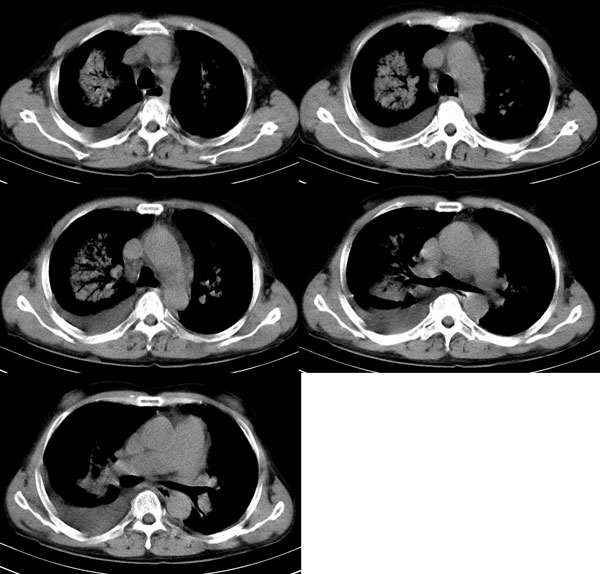

以下是引用wxy7406在2006-11-9 20:45:00的发言:[br]这个人是个男性患者,双侧乳腺明显呈块状,不像就是好东西;双侧肺上叶均见云絮状致密灶,内可见支气管影,右侧肺门去见肿大淋巴结,右侧胸腔见条片状积液。[br]考虑支气管肺泡癌。

以下是引用lkc8963在2006-11-10 0:29:00的发言:[br]大心脏+对称性大片影+双侧胸液,考虑心源性肺泡性肺水肿。请结合临床考虑是何种心脏病。